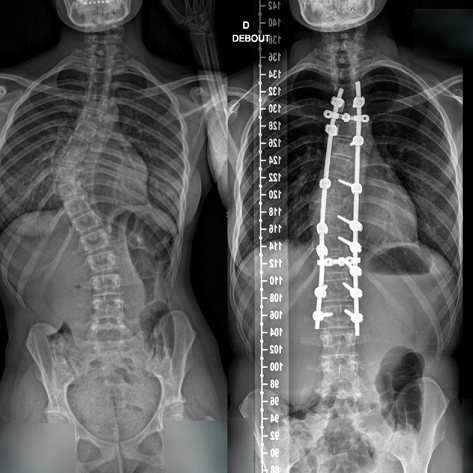

L'intervention consiste à placer une instrumentation métallique comportant une tige, des vis, ou agrafes au contact de la colonne vertébrale afin de corriger la déformation dans les trois plans de l'espace, tout en restaurant les équilibres.

Souvent, le redressement obtenu n'est que partiel compte tenu de l'importante raideur de certaines portions des courbures.

Néanmoins, même une correction partielle et surtout l'évitement de toute reprise évolutive future sont suffisants pour améliorer l'avenir fonctionnel, en comparaison avec une évolution non traitée.

- La correction des courbures s'effectue en redressant progressivement les tiges amarrées à la colonne. Des contrôles radiographiques vérifient la bonne position des implants.